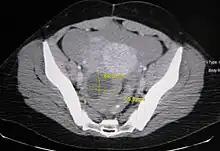

Ovarian cysts are usually diagnosed by ultrasound, CT scan, or MRI, and correlated with clinical presentation and endocrinologic tests as appropriate.[10]

Follow-up imaging in women of reproductive age for incidentally discovered simple cysts on ultrasound is not needed until 5 cm, as these are usually normal ovarian follicles. Simple cysts 5 to 7 cm in premenopausal females should be followed yearly. Simple cysts larger than 7 cm require further imaging with MRI or surgical assessment. Because they are large, they cannot be reliably assessed by ultrasound alone; it can be difficult to see posterior wall soft tissue nodularity or thickened septation due to limited ultrasound beam penetrance at this size and depth. For the corpus luteum, a dominant ovulating follicle that typically appears as a cyst with circumferentially thickened walls and crenulated inner margins, follow up is not needed if the cyst is less than 3 cm in diameter. In postmenopausal patients, any simple cyst greater than 1 cm but less than 7 cm needs yearly follow-up, while those greater than 7 cm need MRI or surgical evaluation, similar to reproductive age females.[11]